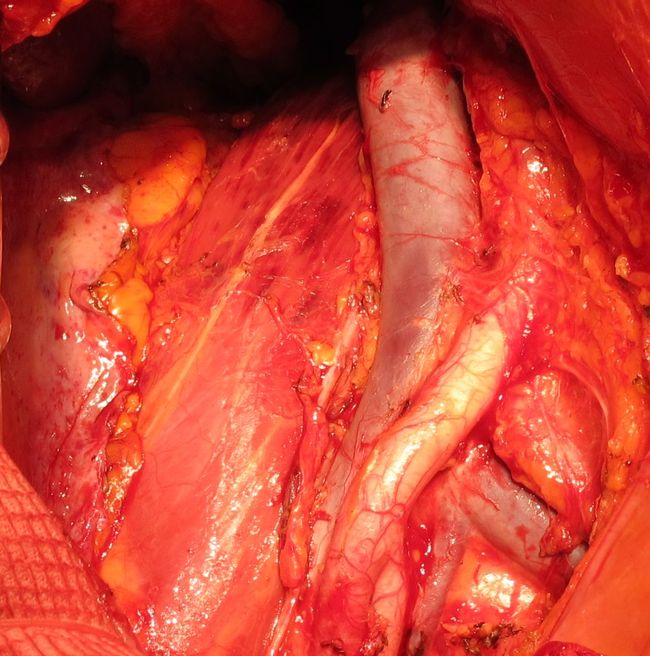

Ложе моочевого пузыря и простаты после цистпростатэктомии